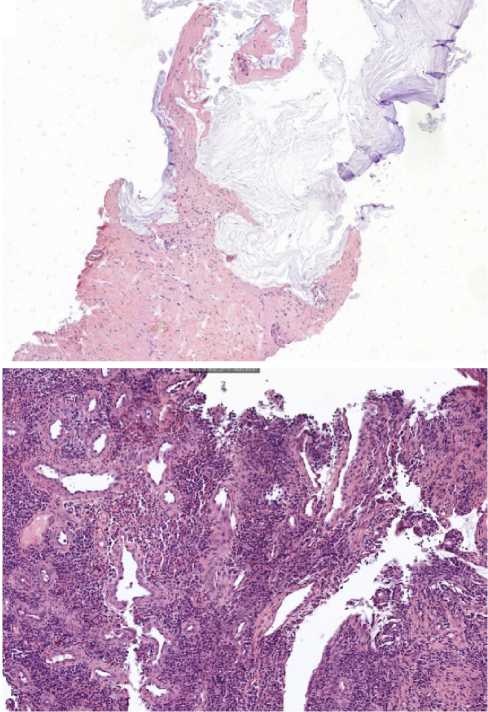

С целью определения патоморфологического регресса в октябре 2023 г. пациенту выполнена чрескожная биопсия опухоли печени под контролем ультразвукового исследования, по результатам которой опухолевой ткани не обнаружено. Гистологический материал был представлен столбиками фиброзной ткани с полями бесклеточного муцина и очаговой лимфоидной инфильтрацией в биоптате.

Помимо этого, пациенту проведена видеоколоноскопия: в просвете верхнеампулярного отдела прямой кишки сохраняется стенозирующая опухоль (рис. 11). По результатам гистологического исследования биоптатов опухолевых клеток не выявлено, фрагменты грануляционной ткани с участками слизистой оболочки толстой кишки (рис. 12).

Рис. 11. Результаты видеоколоноскопиии на фоне иммунотерапии пембролизумабом у пациента 38 лет с диагнозом метастатический колоректальный рак с признаками микросателлитной нестабильности; по данным трепан-биопсии опухолевых клеток не обнаружено (10 января 2024 г.)

Fig. 11. Results of video colonoscopy during immunotherapy with pembrolizumab in a 38-year-old patient diagnosed with metastatic MSI-H colorectal cancer; no tumour cells were detected after trephine biopsy (10 January 2024)

Рис. 12. Результаты морфологического исследования: а - препарат печени (×200), б-препарат кишки (×20) на фоне 14 введений иммунотерапии пембролизумабом у пациента 38 лет с диагнозом метастатический колоректальный рак с признаками микросателлитной нестабильности; опухолевых клеток не выявлено

Fig. 12. Results of morphological examination: a - liver preparation (×200), b - intestine preparation (×20) against the background of 14 infusions of pembrolizumab immunotherapy in a 38-year-old patient diagnosed with metastatic MSI-H colorectal cancer; tumor cells were not detected